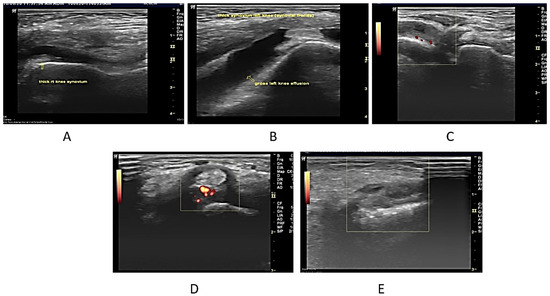

Upon USG evaluation, 47 joints (22.5%) had synovial hyperplasia, 49 joints (23.5%) had joint effusion, and 19 joints (9.1%) had PD signals. A total of 59 joints (10.0%) had USG synovitis (1 or more of the 3 USG abnormalities). USG abnormalities were seen most frequently in the knees, followed by the ankles, elbows, and wrists. A positive Power Doppler was seen in 19 (26%) of the 59 joints with USG synovitis. Most of these patients (n = 16) had grade 2–3 PD signal abnormality and all of them had pain clinically. Only 3 patients had grade 1 PD abnormal signals all three had subclinical synovitis (Figure 1A–E).

Figure 1. (A). Longitudinal USG image of the right knee in a 7-year-old male patient who presented with bilateral knee swelling and mild fever. ESR was also raised. On ultrasonography, both knees revealed synovial hypertrophy with mild effusion in the right knee joint (arrow). (B) Longitudinal USG in a 12-year-old girl child presenting clinically as a case of multiple joint pain and swelling in both knees. On examination, both knees were swollen. ESR and CRP were raised. The ultrasonographic image reveals Joint effusion with Synovial hyperplasia confirming clinical findings. (C) USG image in a 6-year-old Male child with clinically diagnosed JIA having active findings of joint tenderness and elevated local temperature at 2nd MCP. The image reveals synovial hyperplasia with increased vascularity in the thickened synovium on the Power Doppler (Pulse repetition frequency (PRF), which indicated the number of ultrasound pulses emitted by the transducer over a designated period of time of 0.7 kHz. (D) Transverse USG image of the posterior tibial tendon in a 10-year-old male patient of JIA showing peri-tendon synovial thickening and increased vascularity suggestive of tenosynovitis. (E) USG image at the level of the wrist joint in a 10-year-old male child diagnosed with JIA with no evidence of wrist joint involvement clinically showing evidence of synovial hyperplasia (arrow). Power Doppler showed a lack of flow.